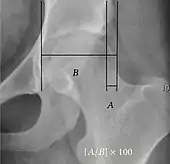

Reimer's migration index.

• Reimer's migration index (MI), also called the femoral extrusion index,[3] is calculated if hip dysplasia is detected. It can be used to indicate hip dislocation. It is the horizontal distance (parallel to the Hilgenreiner Line) between the Perkin line and the lateral border of the ossification center of the femoral head, divided by the horizontal width of the ossification center. The migration index is normally less than 33% by most sources,[9] but 25% and 30% has also been suggested.[10]